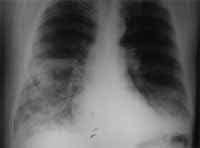

Figura 3. Carcinoma de célula pequeña parahiliar derecho.

Dentro de las características clínicas de este tipo de tumor se encuentran la gran proporción de síndromes paraneoplásicos asociados a éstos, como son el de Eaton-Lambert (17), secreción inadecuada de hormona antidiurética, síndrome de Cushing y otros (23). Dentro de la sintomatología general se pueden presentar síntomas constitucionales (23).